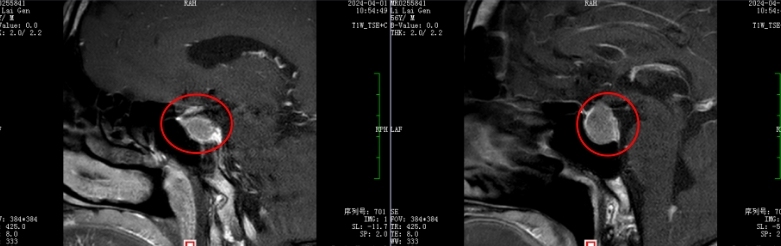

术前MRI检查